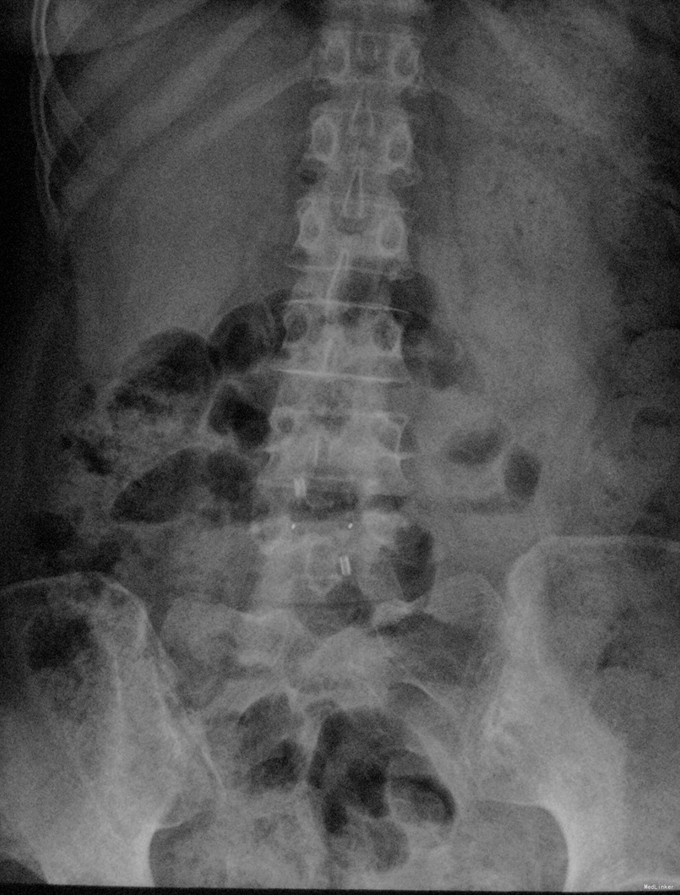

查体:脊柱生理弯曲存在,腰椎活动受限,L4/L5棘突压痛叩痛,叩击痛。双侧直腿抬高试验(-)。双下肢皮肤感觉正常,双侧髂腰肌、股四头肌、双侧胫前肌、踇背伸肌肌力Ⅳ级,腹壁反射、肛门反射正常,两侧膝正常,双侧踝反射未引出。双侧Babinski征(-),双侧皮温及色泽正常,双侧足背动脉搏动良好。 辅助检查:X光片示:动力位片显示腰椎4/5椎间失稳。MRI检查显示:腰4/5椎间盘突出,黄韧带肥厚致椎管狭窄,相应节段硬膜囊受压改变。

诊断:腰4/5椎管狭窄并失稳症。 治疗:给予行后路腰4/5右侧椎板间开窗减压椎间盘摘除并肥厚黄韧带切除+棘突间wallis固定术。